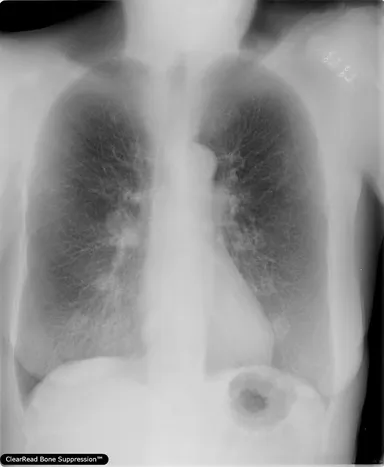

・胸部X線骨組織透過ソリューション/ClearRead BS※1

胸部X線画像の肋骨や鎖骨などの骨組織を透過した画像を生成し、骨組織と重なり検出が困難であった肺結節や異常陰影などの視認性を向上させる。

・「ClearRead BS」:胸部X線骨組織透過ソリューション

- 肺組織の視認性を大きく向上。骨組織透過処理、経時差分画像を生成

- 胸部X線画像上の病変の見落とし防止、気づきの促進

- 読影時の医師の心的負担を軽減

- 国内外あらゆる胸部X線装置で撮影された画像に対応